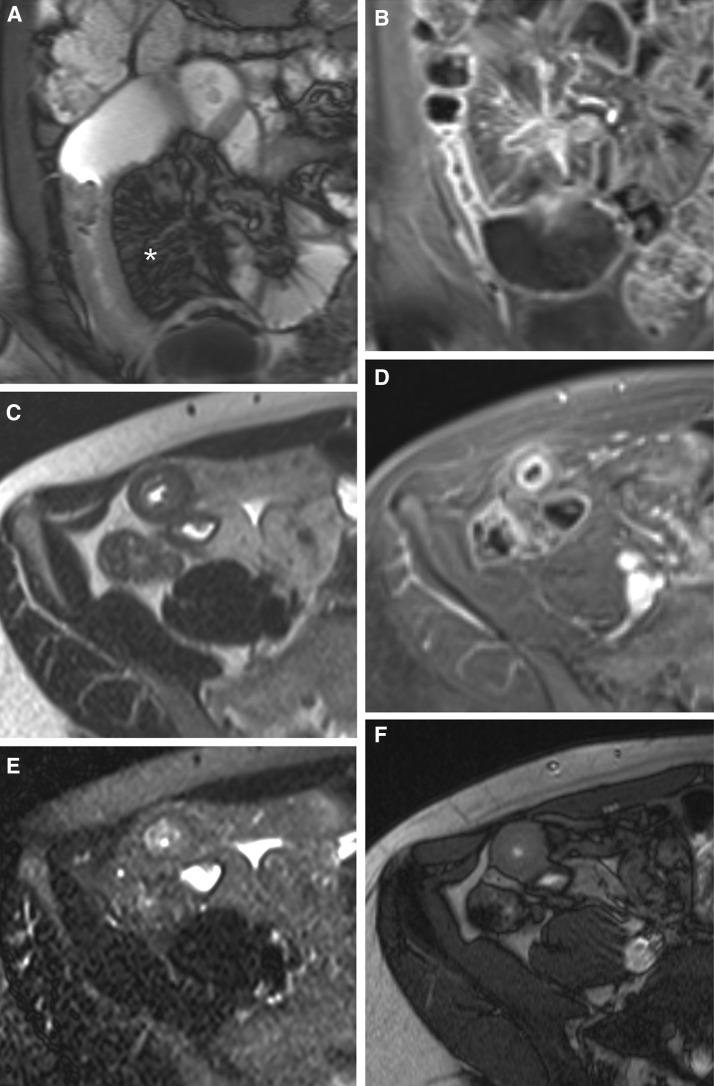

Fig. 2.

The same Crohn’s disease patient as in Fig. 1; nine months later after treatment with adalimumab (HUMIRA, Abbott). A Coronal true-FISP image, B coronal T1-weighted VIBE post contrast image, C transverse HASTE image, D transverse T1-weighted VIBE post contrast image, E axial HASTE image with fat saturation and F an axial true-FISP sequence shows wall thickening and still increased enhancement. Edema has decreased as compared to Fig. 1, indicating less active disease. Prominent engorged vasa recta in the mesentery (comb sign) are also identified (asterisk). The length of the affected segment remains approximately 40 cm. Mapping different sequences by ICT tools would give the radiologist a better overview of the same segment, and a better insight in differentiating between fibrosis and inflammation. Further, objective measurement of the length and/or wall enhancement would help the radiologist and gastroenterologist in therapy monitoring.